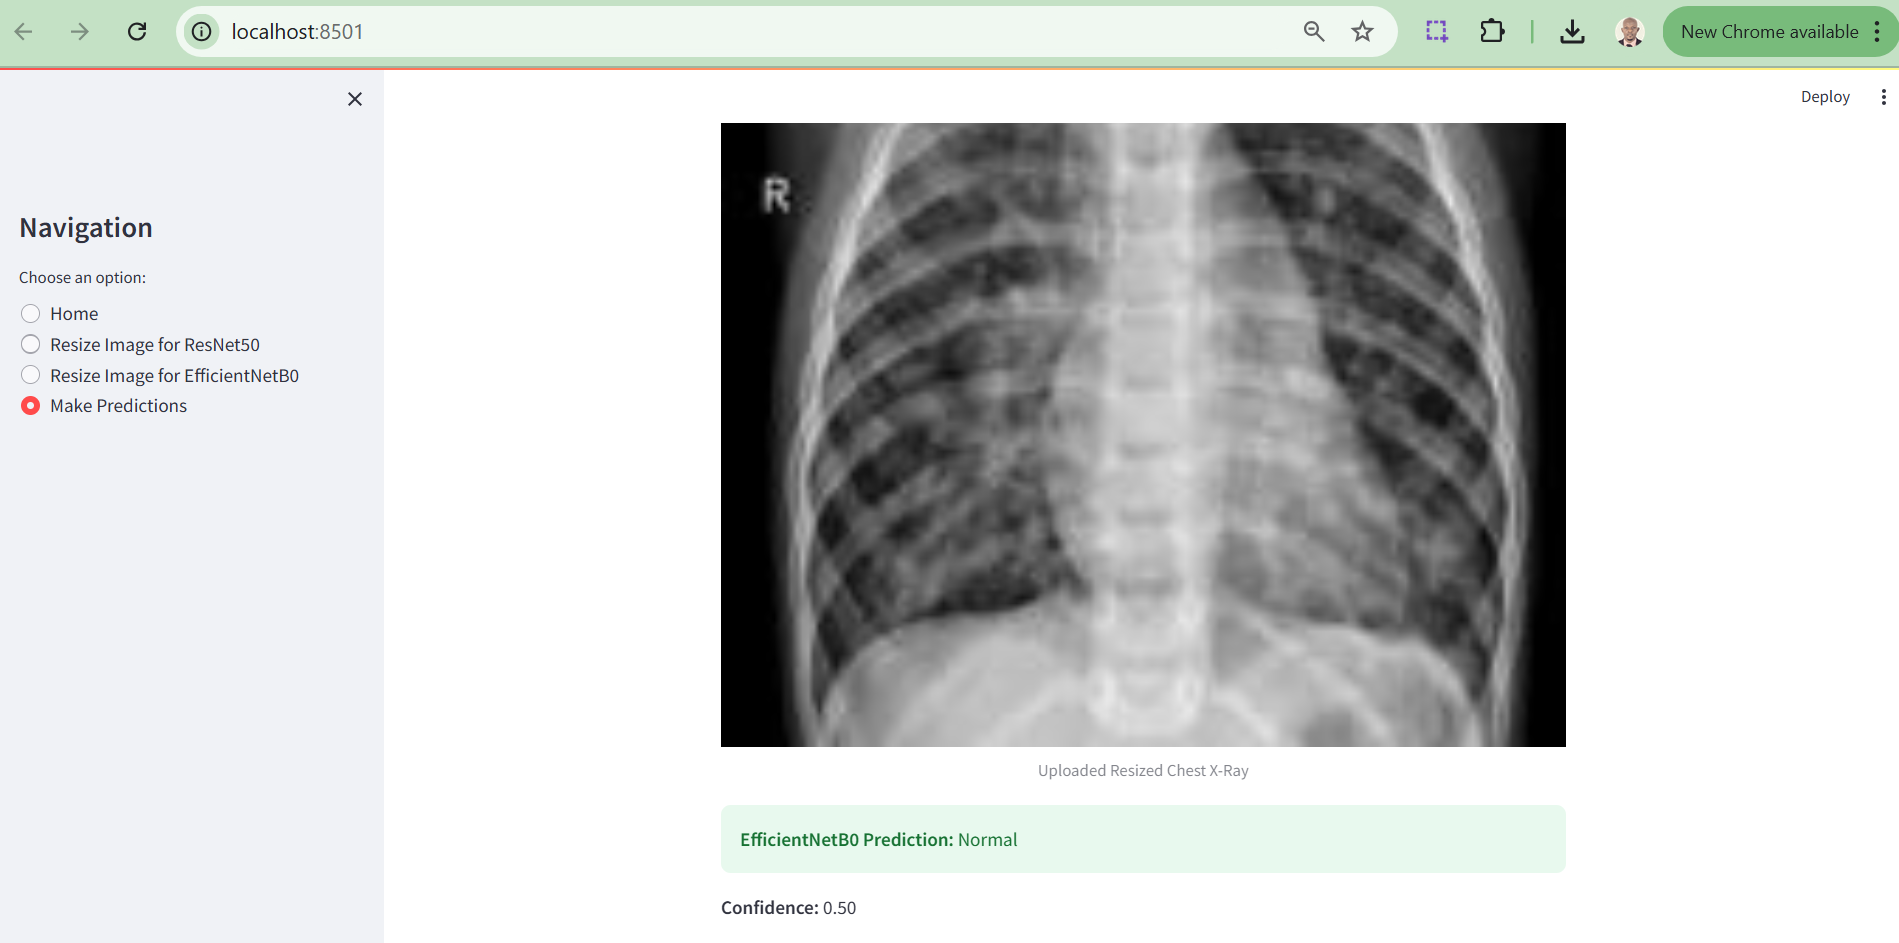

As part of the methodology, a web-based application was developed using Python and Streamlit to enable interactive pneumonia diagnosis from chest X-ray images. This application integrates two state-of-the-art deep learning models, ResNet50 and EfficientNetB0, to predict pneumonia cases. Users can upload chest X-ray images, resize them to the required dimensions for each model, and visualize the prediction results in real time. All application files, including the preprocessing pipeline, trained model files, and deployment scripts, have been committed to a GitHub repository for transparency and reproducibility, fostering further exploration and collaboration in this domain.

As part of this research, a web-based tool was developed to enable clinicians and researchers to easily utilize the trained deep learning models, ResNet50 and EfficientNetB0, for pneumonia detection. This application bridges the gap between advanced computational techniques and clinical usability by providing an interactive and user-friendly interface.

The tool allows users to:

i. Resize Chest X-Ray Images: Resize images to the required dimensions for each model (ResNet50: 224x224 pixels, EfficientNetB0: 150x150 pixels) using the "Resize Image" options in the sidebar.

ii. Upload and Analyze X-Ray Images: After resizing, users can upload the processed image and receive diagnostic predictions with associated confidence scores.

iii. Visualize Results: Users can compare the predictions of both models side-by-side, enabling insights into their performance and clinical applicability.

Below are screenshots of the tool interface:

Figure 9. Prediction Output Section

The results of this study reveal the strengths and limitations of leveraging deep learning models, EfficientNetB0 and ResNet50, for pneumonia detection. EfficientNetB0 demonstrated consistent performance when tested with properly resized images, highlighting its robust design for transfer learning and medical imaging tasks. However, its reliance on exact input dimensions underscores a limitation for real-world applications, where data may not always conform to predefined standards. ResNet50, on the other hand, showcased potential but suffered from implementation errors during prediction, a hiccup reflective of the constraints of research timelines rather than its architectural capability.

On a lighter note, the deployment of these models into a Streamlit web application offers a glimpse into the practical utility of AI in medical diagnostics. Though not without its quirks, one model excelling while the other remains uncooperative - it adds a humanising layer to this research. After all, even AI models can have bad days! Future iterations will refine these limitations, paving the way for a seamless integration of AI into clinical workflows.

Further notable limitation of this research’s web implementation is that the EfficientNetB0 model successfully generates prediction results only when users upload pre-optimized X-ray images, whereas the ResNet50 model currently fails to produce predictions due to an unresolved error. While significant efforts were made to address this issue, time constraints prevented its resolution within the scope of this research. This limitation will be prioritized and rectified in subsequent phases of the study to ensure a fully functional diagnostic tool.